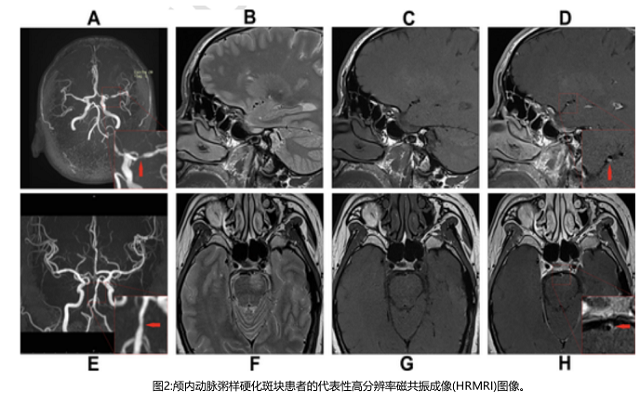

高分辨率磁共振成像(HRMRI),一種處理血流和血管壁對(duì)比的無(wú)創(chuàng)成像技術(shù),作為一種可靠的可視化血管壁形態(tài)和病理的成像方法,在無(wú)創(chuàng)體內(nèi)分析中獲得了突出的地位。HRMRI突破了傳統(tǒng)體內(nèi)血管檢查技術(shù)的局限性,為我們提供了有關(guān)動(dòng)脈粥樣硬化組成的信息,如炎癥、壞死核心的存在和斑塊內(nèi)出血。HRMRI上顱內(nèi)斑塊的異質(zhì)性增強(qiáng)是斑塊不穩(wěn)定的標(biāo)志,與有癥狀的顱內(nèi)動(dòng)脈粥樣硬化患者近期的缺血事件和卒中復(fù)發(fā)密切相關(guān)。該研究基于HRMRI研究HDL亞組分與顱內(nèi)大動(dòng)脈粥樣硬化斑塊特征之間的關(guān)系。

病變部位定義為由MCA動(dòng)脈粥樣硬化病變引起的管腔狹窄最嚴(yán)重的水平(圖2)。通過(guò)血管-腦脊液界面自動(dòng)計(jì)算血管面積(VA)。管腔面積(LA)由血管-血液界面計(jì)算。選擇斑塊最厚的切片來(lái)測(cè)量直徑。壁面積(WA)計(jì)算為血管面積減去管腔面積。斑塊面積為病變部位的WA減去參考部位的WA。斑塊負(fù)擔(dān)計(jì)算為斑塊面積/病變部位血管面積× 100%。狹窄率公式為(病變部位1-LA /參考部位)× 100%。重構(gòu)指數(shù)(RI)是指病變部位血管面積與參考部位血管面積之比。陽(yáng)性重構(gòu)(PR)定義為RI > 1.05;負(fù)重構(gòu)(NR)定義為RI < 0.95;中度重構(gòu)定義為RI在0.95 ~ 1.05之間。